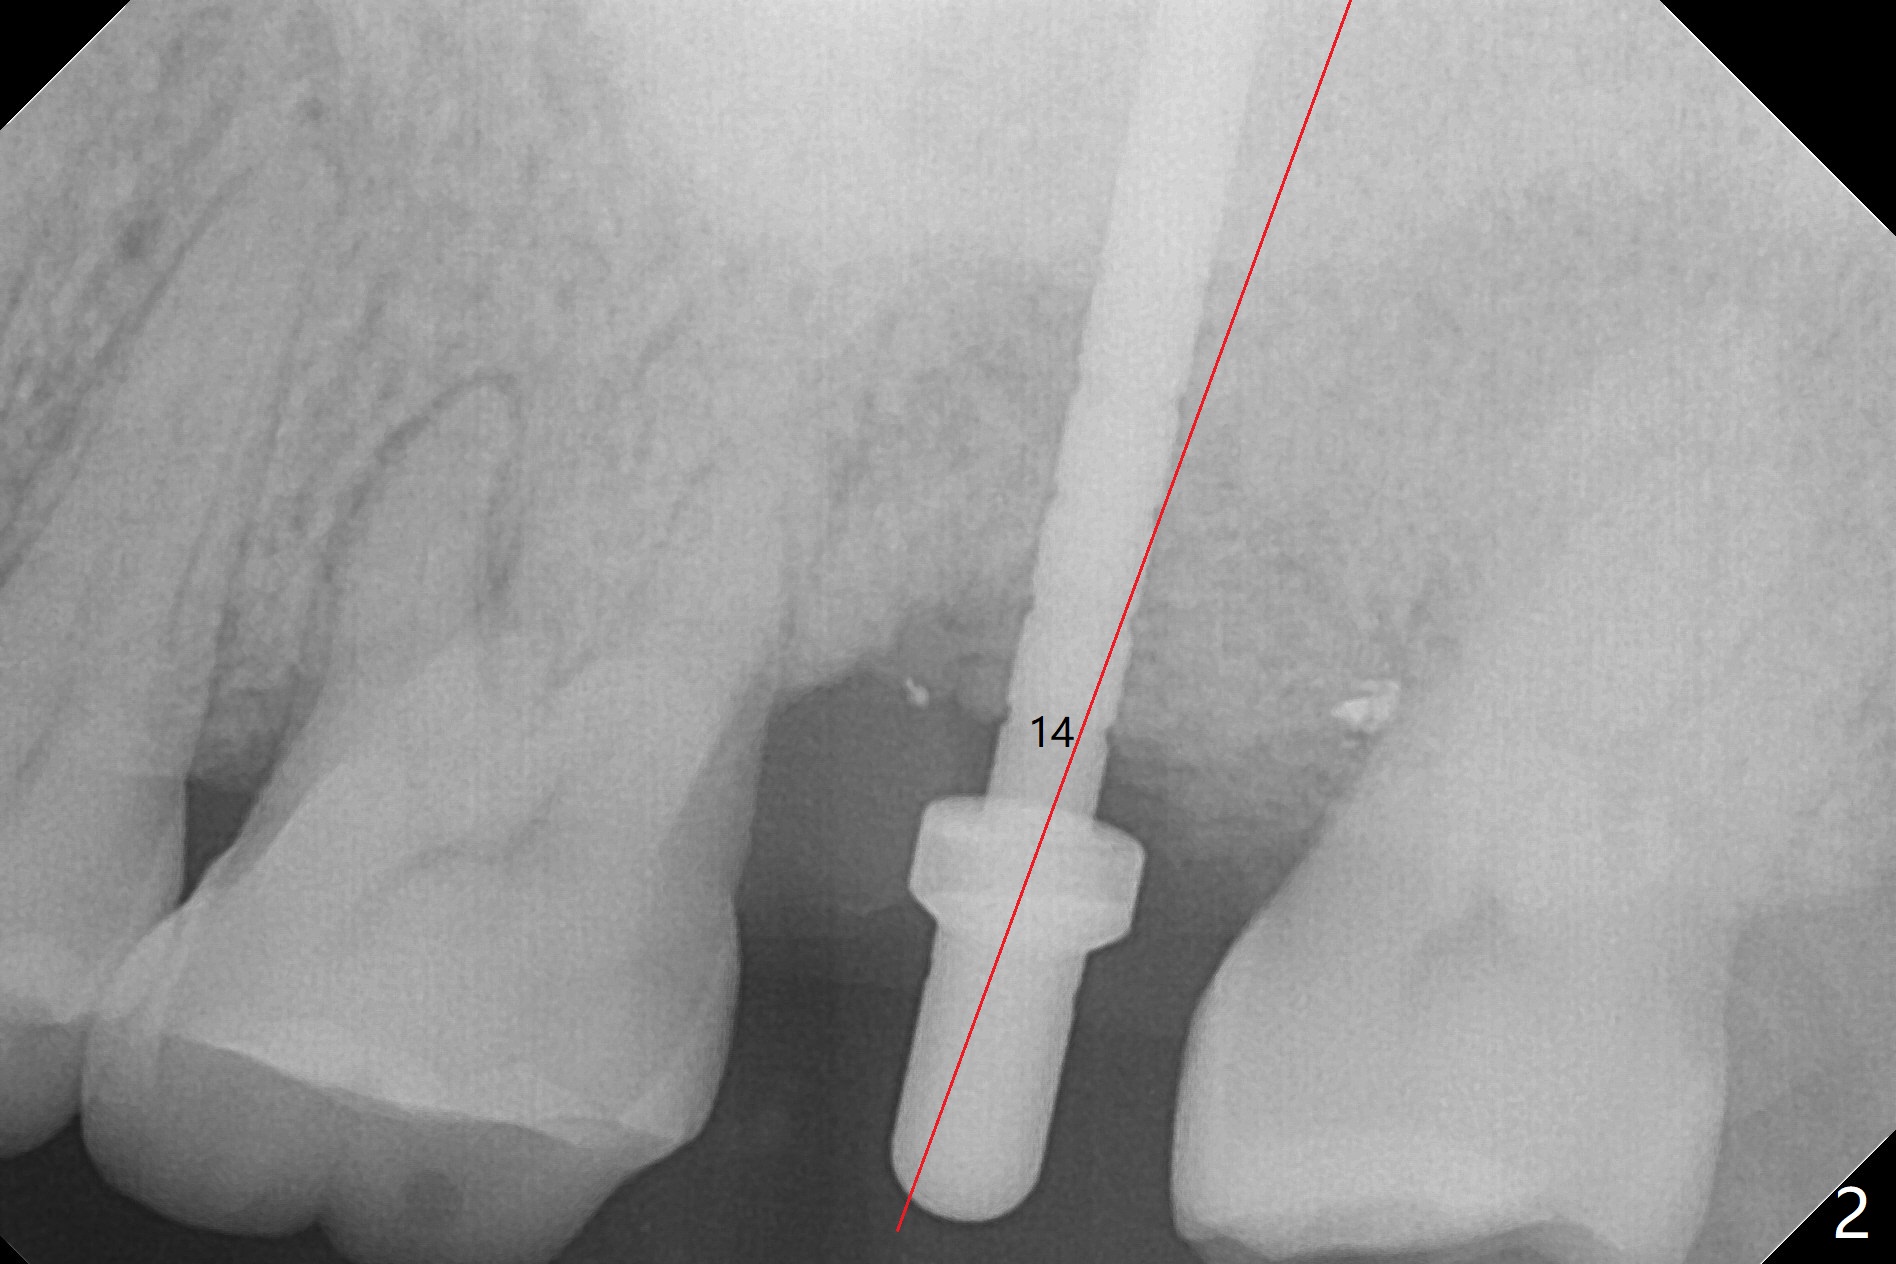

When the patient returns for the tooth #15 extraction and implant, the mesiobuccal residual root has been expelled, while the distobuccal and palatal roots seem to have extruded (Fig.1). The mesial portion of the gingiva (G) is intact and thick. The trajectory of the initial osteotomy is to be changed as shown by red line in Fig.2. The 3.8 mm drill appears to be distal (Fig.3). With mesial bone removal with Lindamann bur, the position of the final implant (5x13 mm) is within normal limit (Fig.4 (50 Ncm)). Because of the thick mesial gingiva (Fig.4 G) and placement of the 5.5x4(2) mm abutment, insertion of mixture of autogenous and Vanilla Graft (*) into the mesial aspect of the implant is difficult (Fig.4 >). Further pushing of the bone graft from the buccal and palatal socket gaps results in more ideal packing (Fig.5 >). If the bone graft were placed first, packing would have been easier. An immediate provisional is fabricated to prevent further mesial shifting of the 3rd molar (Fig.1 arrow). The implant remains stable, while the provisional and abutment are loose 3 months 1 week postop (Fig.6). Impression is taken after abutment cleaning and retightening. Because of the long implant (13 mm), a permanent crown can be cemented early (3 months 20 days postop, Fig.7).